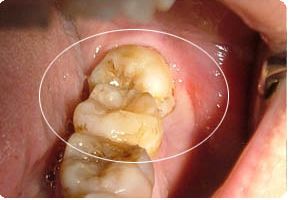

1、牙齿情况:在拔智齿前,牙医会对患者进行详细的口腔及身体检查,对拔智齿禁忌人群进行排除,如果口腔内有龋病、炎症或牙结石等情况则需进行适当的处理,从而加增加了拔智齿的费用,而由于每个人牙齿健康状况的不同,导致了拔智齿费用不同。

2、智齿位置:智齿所处的位置、需拔数量、生长怪异程度、病变程度的不同,其拔牙难易程度不同。有些患者智齿结构较为复杂,在拔智齿前需进行拍X光片以了解智齿的底部结构。一般说来,上颌智齿结构简单,较容易拔除,因此上颌拔智齿价格较下颌拔智齿价格便宜。